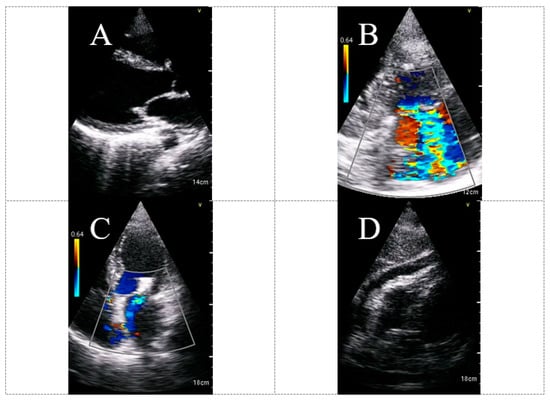

Different protocols were proposed for cardiac POCUS [20]. HUD-based echocardiography has a significant role in the diagnosis of COVID-19 associated abnormal processes, including hyperdynamic cardiac function, stress-induced cardiomyopathy, RV enlargement, pericardial effusion, acute pulmonary hypertension (secondary to pulmonary embolism or to the detrimental effects on the lung parenchyma) and diffuse myocardial inhibition, among other less common diagnoses. Figure 5 shows examples of abnormal findings using HUD for echocardiography real-time assessment among COVID-19 patients.

Figure 5.

HUD acquired echocardiographic images in COVID-19 patients demonstrating abnormal findings: Dilated LV with reduced systolic function (A), severe MR (B), status post MitraClip transcatheter mitral valve repair (C) and pericardial effusion (subcostal view) (D). The imaged were acquired using the Vscan Extend with the Dual Probe, General Electric. Abbreviations: HUD, hand-held ultrasound device; LV, left ventricle; MR, mitral regurgitation.